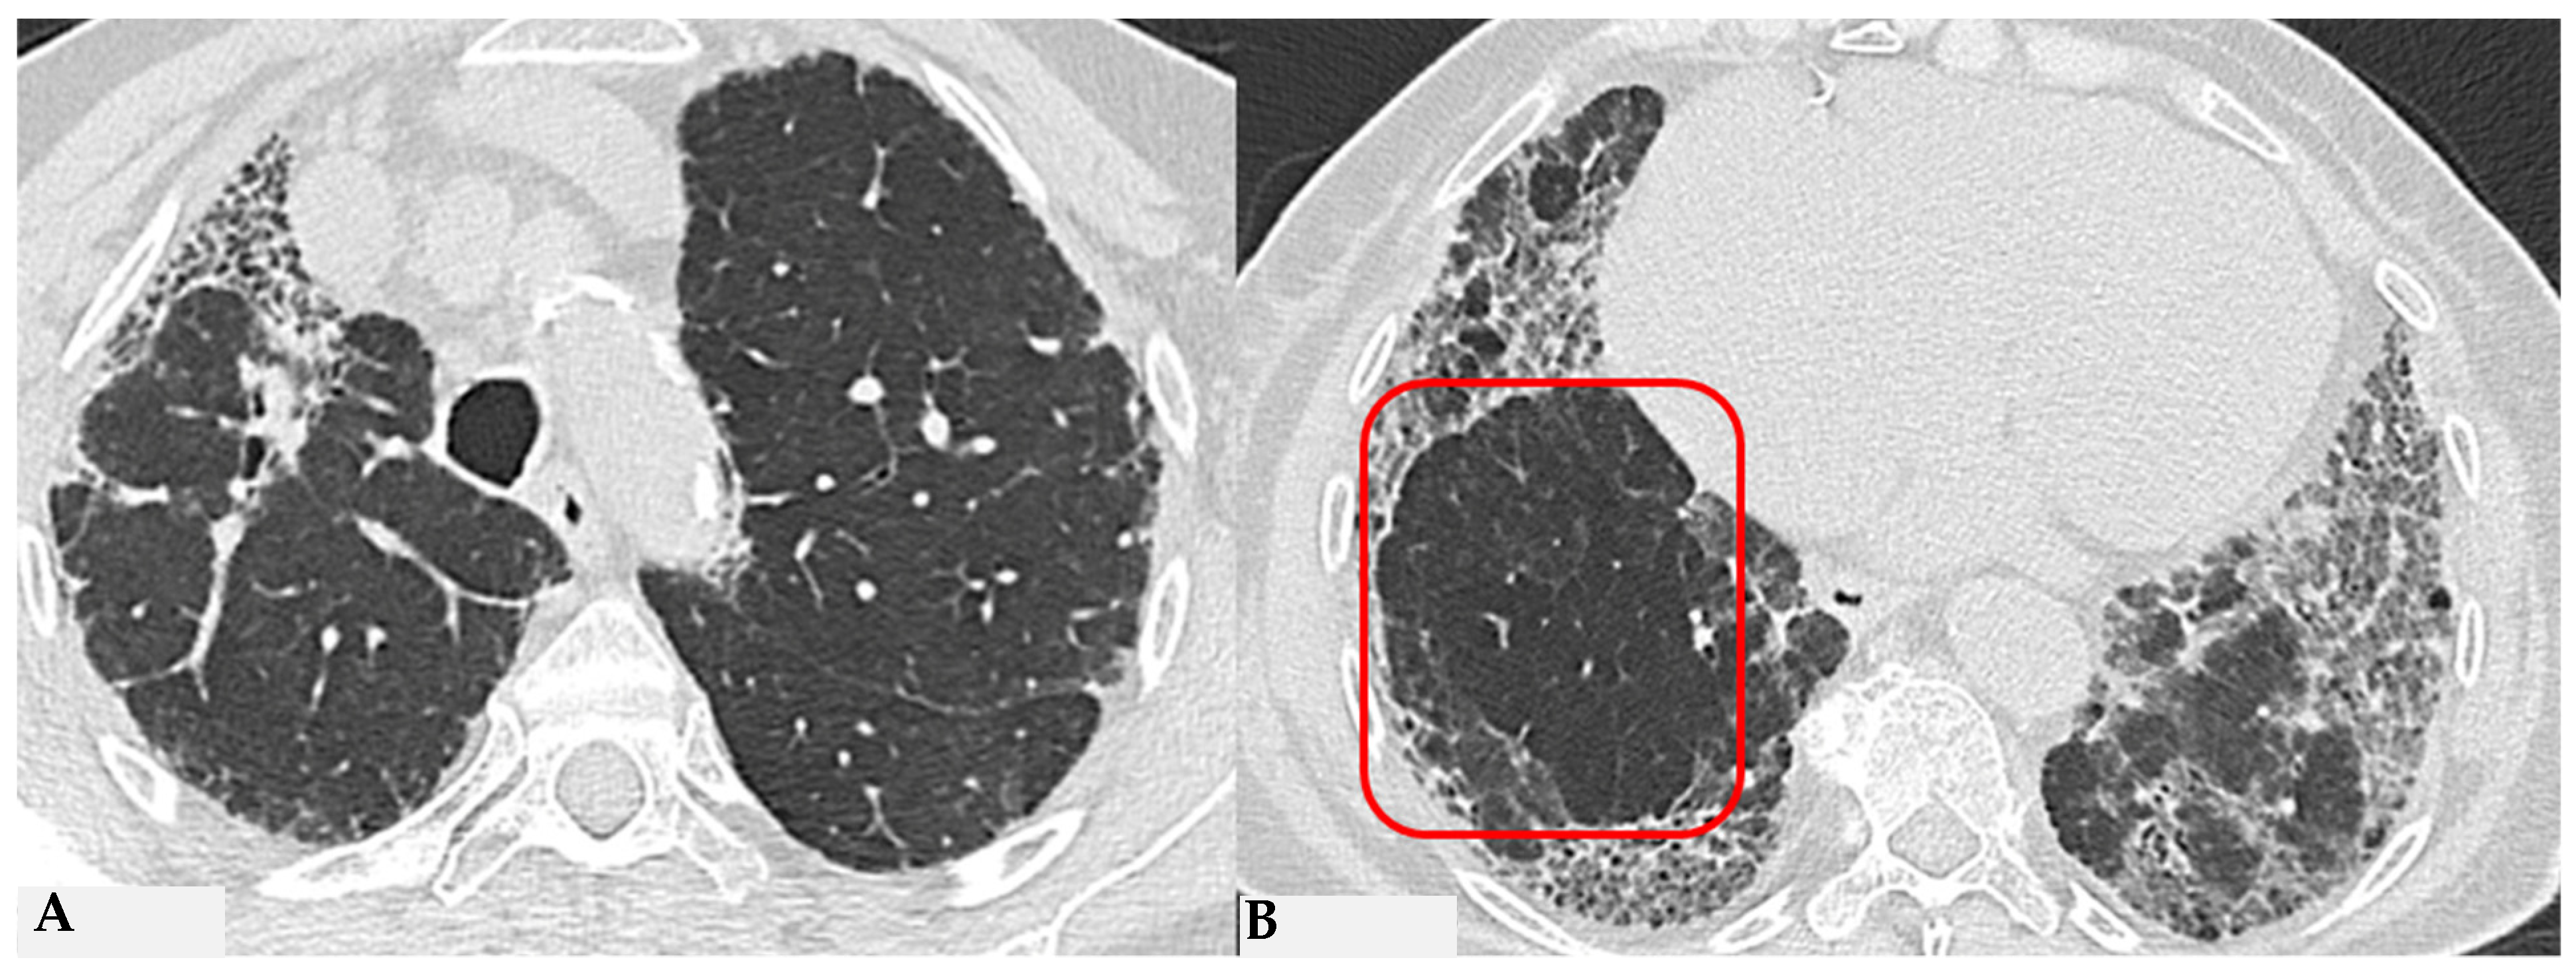

Similar observations can also be made regarding honeycombing, the terminal process of chronic and progressively realized damage in multiple diffuse lung pathologies. In HP, compared to IPF, honeycombing features gross characteristics, expressed with a “new” term of the semiotic HRCT called “exuberant honeycombing”, with a moderate increase in the size of lung cysts and a radiological UIP pattern. Despite increased knowledge about ILDs, “exuberant honeycombing” in HP remains a diagnostic challenge in the absence of suggestive secondary form history and is also visible in other diseases, for example, CTD-ILDs (Figure 4).

Figure 4.

End-stage lung: HRCT magnification of right lower lobes in two different patients. Profuse honeycombing in chronic hypersensitivity pneumonitis (HP) with evidence of multiple multilayered pulmonary cysts ranging in size from a few mm to 10 mm (A); honeycombing in idiopathic pulmonary fibrosis (IPF) characterized by minute clustered pulmonary cysts coexisting with subpleural distribution of traction bronchiectasis and bronchiolectasis (B).